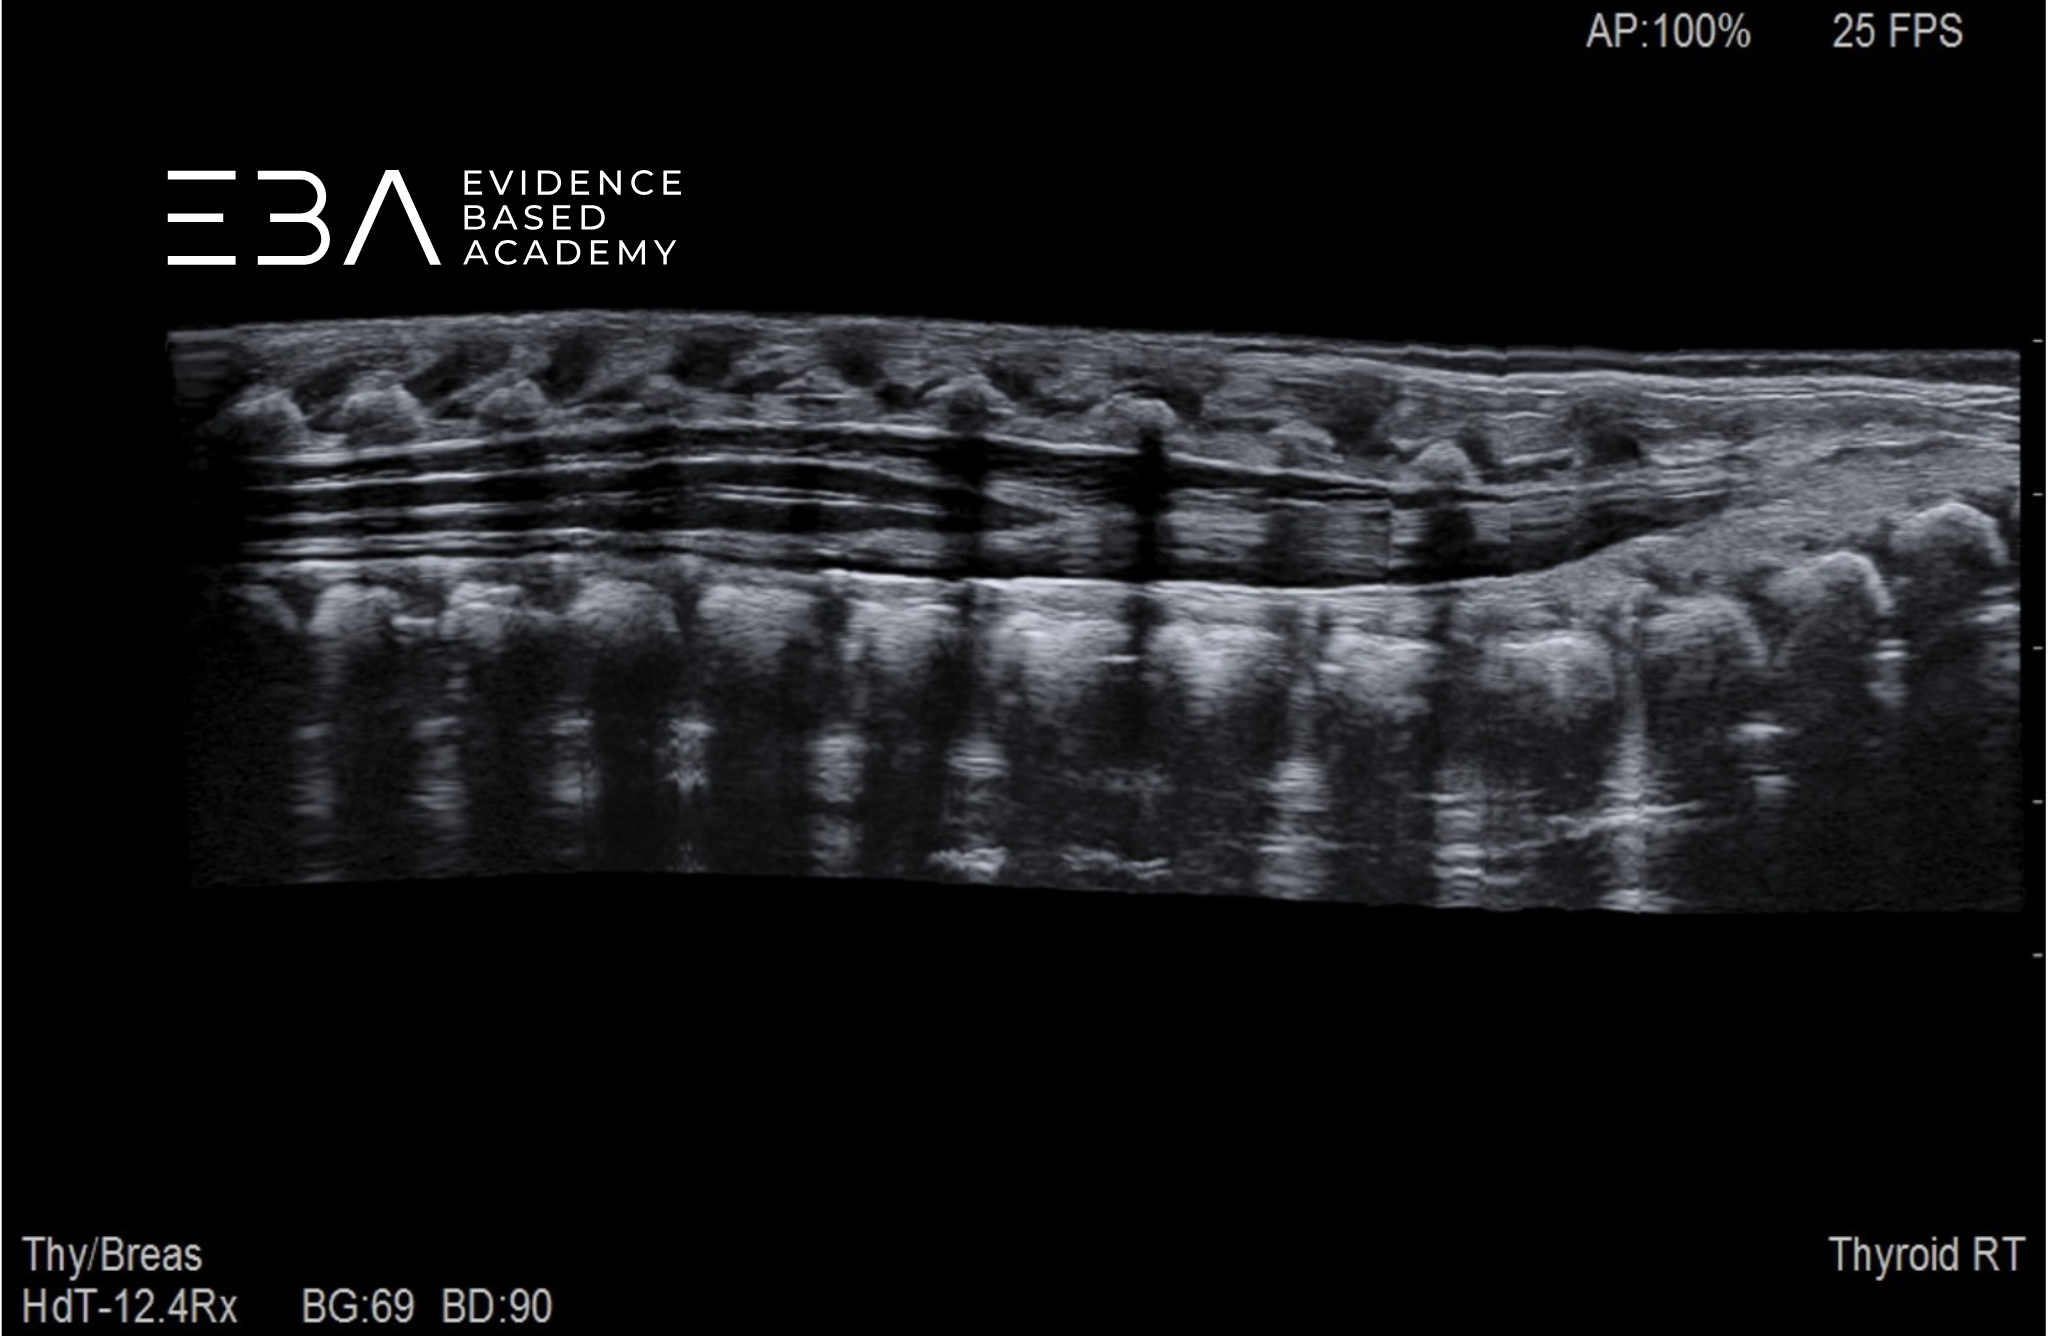

fot. 1

Przekrój podłużny kanału kręgowego – obrazowanie panoramiczne.